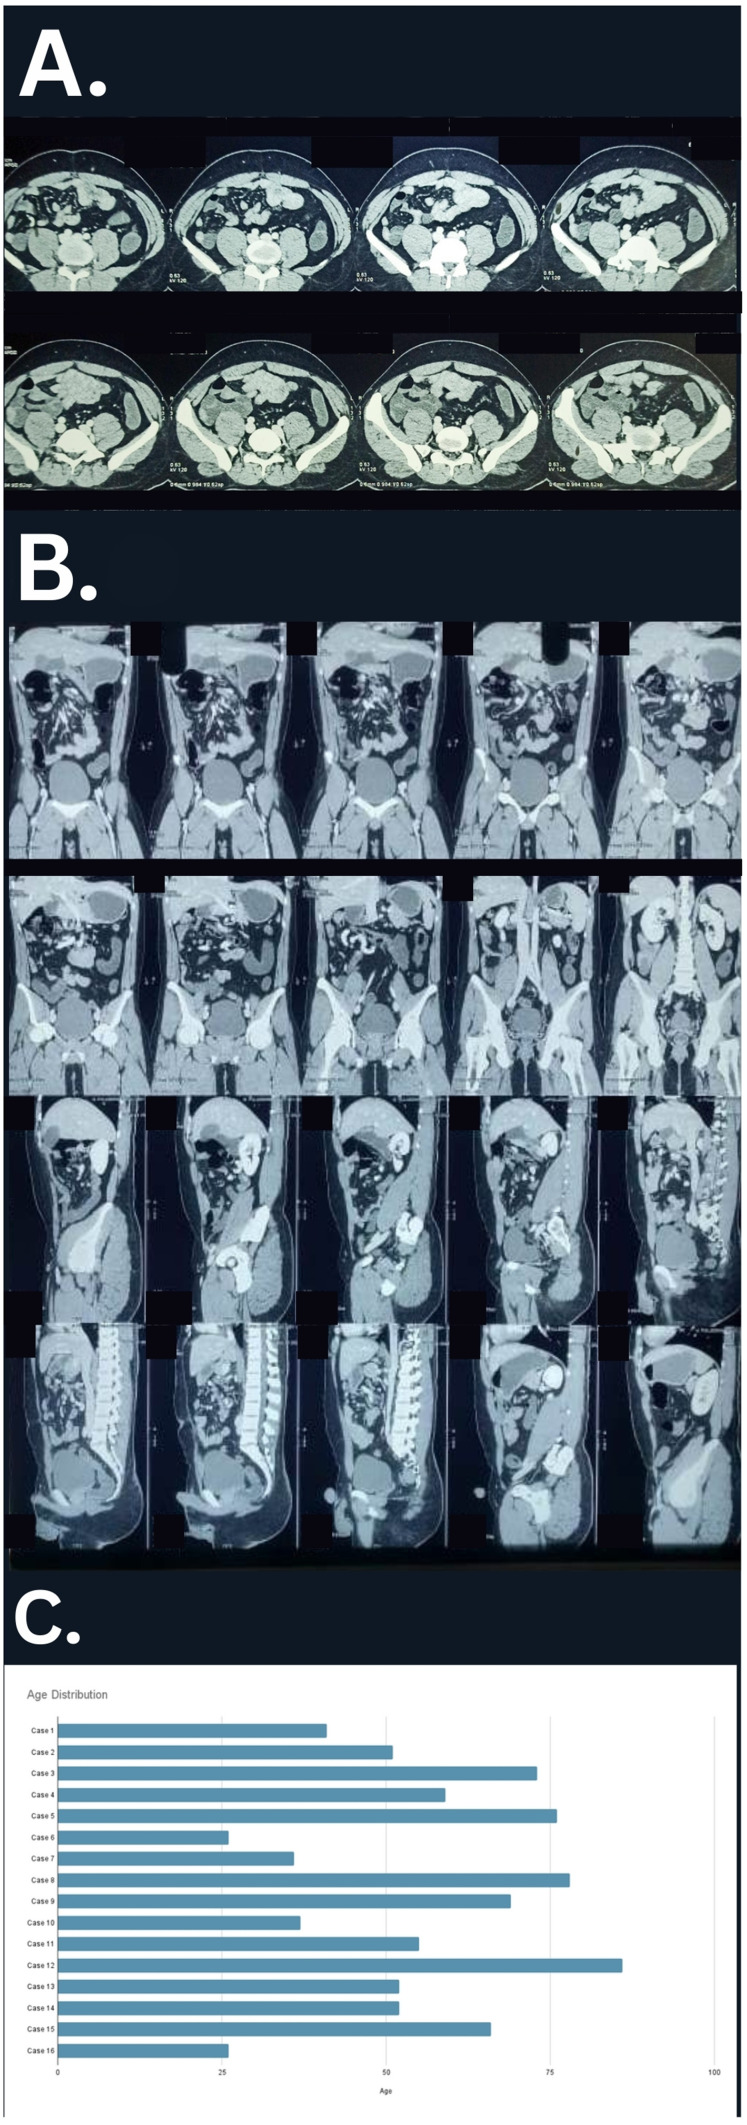

Case presentation: A 26-year-old male presented with acute right lower quadrant abdominal pain and vomiting. He had a similar episode seven years prior that self-resolved. Physical examination revealed generalized abdominal tenderness, guarding, and mild distention. Imaging studies, including abdominal ultrasound and CECT, confirmed midgut volvulus due to nonrotation. The patient underwent exploratory laparotomy and Ladd's procedure, leading to an uneventful recovery and discharge on postoperative day seven.

Results: The mean age at presentation was 55.19 years (range: 26-86), with a slight male predominance (56.2%). The most common symptoms were acute abdominal pain (50%) and vomiting (31.25%). Notably, 50% of cases were identified incidentally during evaluations for unrelated conditions or procedures. CT scans confirmed diagnoses in 87.5% of cases. Positional anomalies included right-sided small bowel and left-sided colon in 37.5% and reversed SMA/SMV relationships in 33%. Ladd's procedure was performed in 25% of cases.